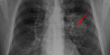

تأتي هذه الدراسة في مواجهة توصيات طبية أكثر تحفظا تأخذ في الاعتبار فوائد وأضرار الفحص بالأشعة السينية